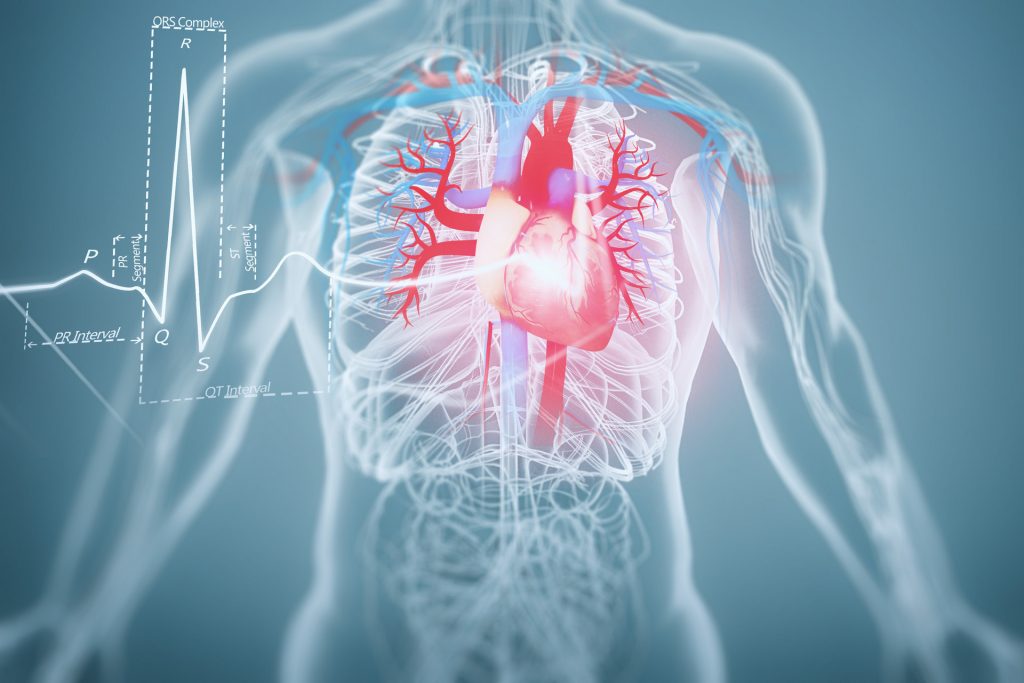

心血管深度CTA筛查

无创检查,风险低,安全性高,操作简便,花费少且患者无需住院。一次检查可获得冠脉形态、心脏结构、功能、心肌活性等多种信息

解剖结构精准呈现: 能无创、清晰地显示冠状动脉的起源、走行及是否存在先天性解剖变异,为制定介入或外科手术方案提供至关重要的“路线图”。

血管状态全景评估: 利用多种先进的影像重建技术,实现多角度、全方位观察。不仅能准确判断血管腔内的狭窄程度,还能同步评估血管壁的斑块性质(如软斑块、钙化斑块)、厚度及其与周围组织的关系,实现“由内到外”的综合分析。

特殊成像优势显著: 对冠状动脉钙化积分评估、腔内血栓的检出以及血管内植入支架的形态、位置及通畅性显示具有显著优势,是术后随访和风险评估的关键工具。